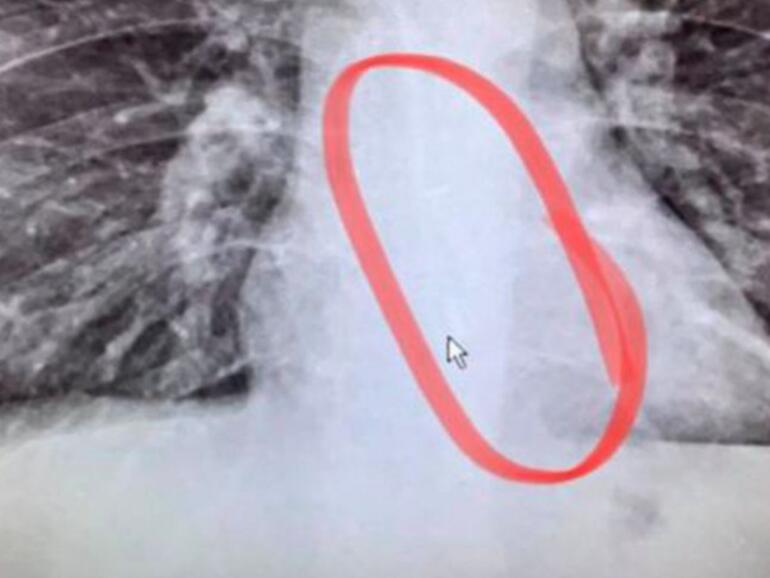

Seine Familie witzelte schon, dass er den einen AirPod vielleicht verschluckt habe, aber dies kam Gauthier absurd vor. Dennoch beschloss er den Weg in die Notaufnahme anzutreten. Dort wurde er geröntgt und dabei trat tatsächlich der verlorene Ohrhörer in Erscheinung. Dieser hatte sich in seiner Speiseröhre verkeilt und ließ nicht mehr durch. Mit einer Endoskopie entfernten die Ärzte schließlich den AirPod, sodass Gauthier nach Hause zurückkehren und weiter Schnee schieben konnte.